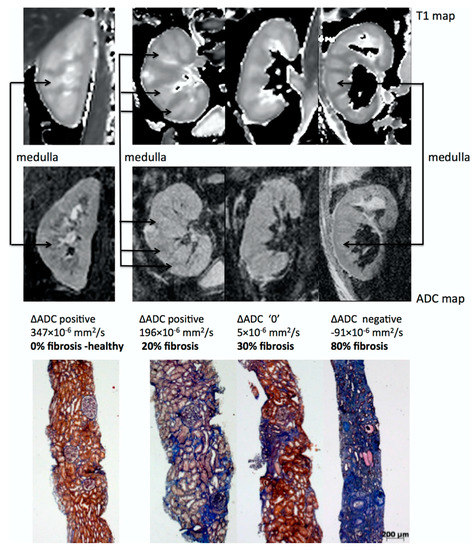

One of the most promising applications of DWI is the estimation of renal fibrosis in chronic kidney disease (CKD) patients, which is a key prognostic marker for renal function decrease and the progression of CKD. This assertion has two main arguments. First, ADC values correlate with renal function [118,119,120,121,122,123] and DWI is an accurate non-invasive imaging technique for the early diagnosis and staging of CKD, as shown by a meta-analysis [124]. Second, numerous clinical studies have directly demonstrated that cortical ADC values as well as other diffusion related parameters are linearly correlated to renal fibrosis in CKD patients, as assessed by renal biopsy [105,125,126,127,128,129,130,131,132,133]. As fibrosis increases, the cortical ADC values decrease much more than the medullary ADC values, resulting in an inversion of the cortico-medullary difference of ADC or so-called ΔADC which can be observed in the images [129] (see Figure 7). DWI can also differentiate between the different levels of fibrosis [127,128].

Figure 7.

Representative biopsy and MR images in chronic kidney disease patients. Morphological MOLLI T1 maps used for the positioning of the regions of interest (top row) and ADC maps (lower row) for three patients showing different ΔADC cases: positive, zero and negative; along with the corresponding fibrosis levels from histology (Masson trichrome staining). The inversion of the corticomedullary ADC difference meets the increasing degree of renal fibrosis. Adapted from Figure 7 of Ref. [129] with permission. Copyright 2016 Springer Nature.

The exact physiological and mechanistic explanation for the link between DWI values and renal fibrosis is not fully understood but may be the result of two main synergetic events occurring in the development of renal fibrosis in CKD: (1) an increase in cellular density and the extra-cellular matrix which reduces free water motion and (2) a reduction of microvascular perfusion and filtration-induced water mobility expected with impaired renal function [134].